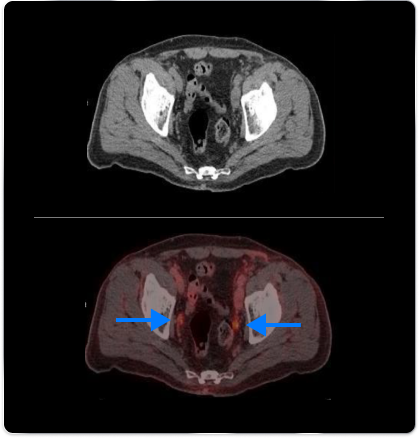

High-risk patient with newly diagnosed prostate cancer

Age

63

PSA (ng/mL)

26

Gleason Score

4 + 3

PYLARIFY may have helped prevent overtreatment